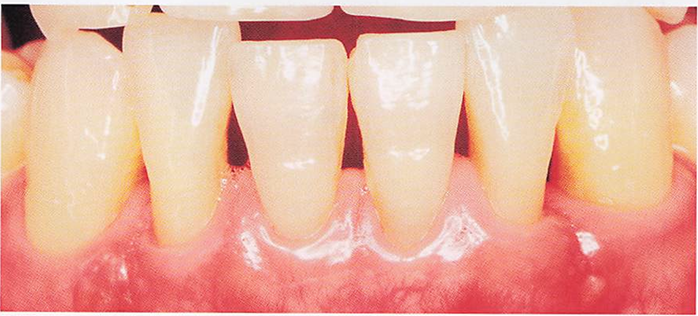

54歳の女性。ブラッシング時に下顎左側中切歯に痛みを感じることを主訴として来院した。同歯の唇側歯頚部を探針で擦過すると一過性の痙痛を確認した。初診時の口腔内写真を別に示す。 露出根面に塗布するのはどれか。1つ選べ。